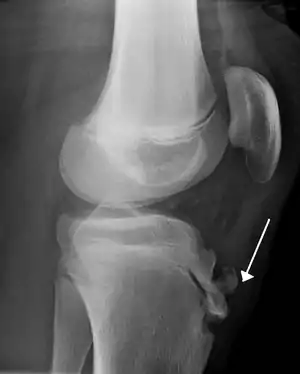

| Lateral view X-ray of the knee demonstrating fragmentation of the tibial tubercle with overlying soft tissue swelling. | |